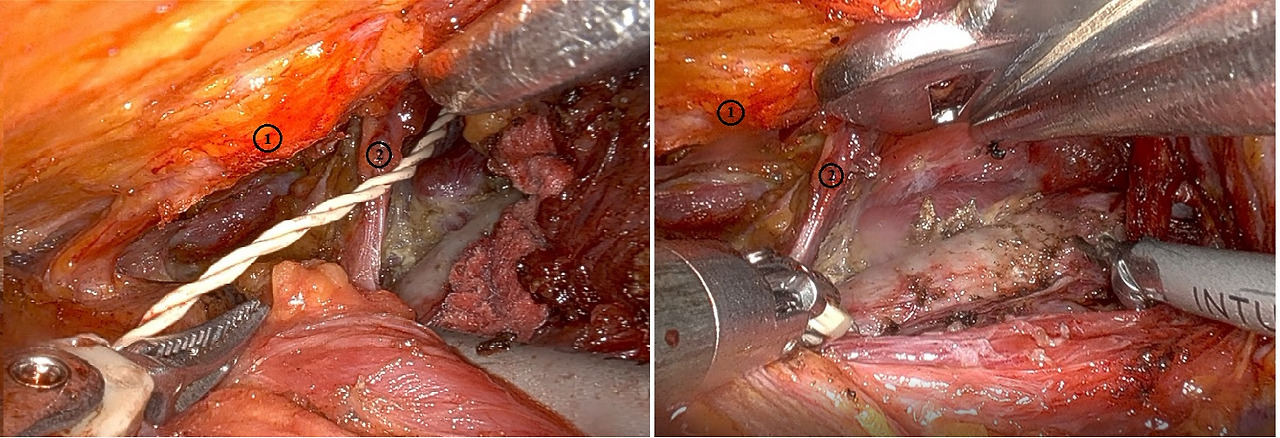

그런데 어느 날인가 작업공간을 만들던 중에 원칙적으로는 목빗근 (sternocleidomastoid)의 흉골부와 쇄골부 사이로 박리를 해야 하는데, 그렇지 않고 그 보다 더 위쪽 (환자편 배 쪽)에 있는 띠근육과 목빗근의 흉골부 사이로 박리를 한 거야. 아래의 수술 부위 사진으로 설명을 하면, 사진의 ①은 띠근육 (sternothyroid & sternohyoid muscle)이며 ②는 목빗근 (sternocleidomastoid)인데, 원래는 사진처럼 못빗근사이로 박리가 되어야 하는데 그 보다 위쪽 (배 쪽)인 ①과 ②사이로 박리가 된 거야. 그동안 몇 백건의 수술을 하였는데 초년병일 때나 하는 실수라 어이가 없었지. 그런데 수술이 끝나고 곱씹어 생각하던 중 이 사진 속에 경부 중앙 림프절 절제술의 한계에 대한 답이 있었던 거야. 사진에서 천장 쪽(배 쪽)의 띠근육 ①과 목빗근 ②사이의 경부중앙림프절이 목빗근의 흉골부에 가려져서 충분히 제거되지 않았던 것이야.

그 후로 어떻게 하면 저 부위를 더 제거할 수 있을지 고민했지. 그래서 ②의 근육에 가려져서 보이지 않은 곳을 보기 위해 내시경(scope)의 각도를 조절했어. 그리고 그러한 각도에서 로봇 팔이 잘 작동하도록, 서로 부딪히지 않도록 개수나 로봇 팔의 위치 등을 조절했지. 물론 액와부의 절개선도 위치를 좀 바꾸었어. 이러한 시도들로 최근 시행한 액와부 접근법에서는 이러한 단점을 보완하여 포획된 경부중앙 림프절 개수가 경부절개(open)에 비해서 통계적으로 유의한 차이를 보이지 않았어(아래 표 참고). 그러나, 이러한 방법을 쓰더라도 경부 중앙 구획의 제7부위까지는 제거할 수 없어. 이러한 단점은 경구접근법(TO)에 극복할 수 있는데 이는 차후 논하도록 하지요.